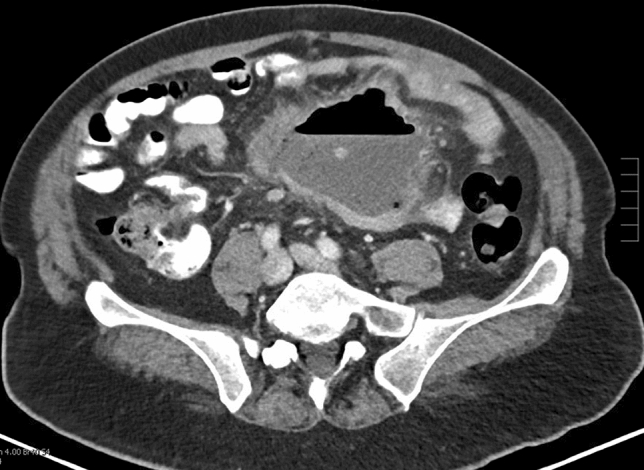

Methods and Procedures: Twenty-four patients underwent abdominal wall reconstruction (AWR) between January 2017 and June 2022 by a single surgeon at our institution. Lifestyle information (smoking, diabetes, and obesity status) and procedure-related metrics (pre-operative botox use, hernia characteristics, and mesh type) were obtained. The ellipsoid formula (V = 4/3ABC) was used to calculate volume of the hernia sac (VIH) and abdominal cavity (VAC) (Fig. 1). Measurements at initial visit and time of surgery were compared and analyzed using a two-tailed T Test (p < 0.05 signified significance).

Results: Pre-operative counseling results are shown in Table 1. Procedure-related metrics are shown in Table 2.

Fig. 1 Hernia sac measurements for calculating VIH (Left to right: axial, sagittal, coronal)